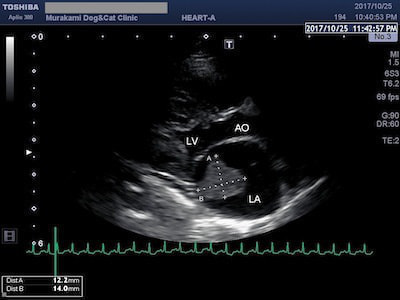

拘束型心筋症(RCM)

肥大型心筋症(HCM)と並んで、猫によくみられる心筋症の一つが拘束型心筋症(RCM)です。HCMと違って心筋の肥大は認められませんが、心内膜の線維化や、心室内に過剰な線維性構造物(過剰調節帯)が認められ、心臓の動きが悪くなる(拘束される)のが特徴です。

RCMに伴う胸水と左房内血栓

RCMでは心室の動きが拘束されることにより拡張機能が妨げられ、僧帽弁逆流や三尖弁逆流が生じた結果、左房拡大や右房拡大が顕著に認められます。拡張した心房内では血流の鬱滞や乱流が生じるため、肺水腫や胸水の貯留、血栓が生じやすくなります。治療には血管拡張薬や利尿剤、血栓予防薬を用います。